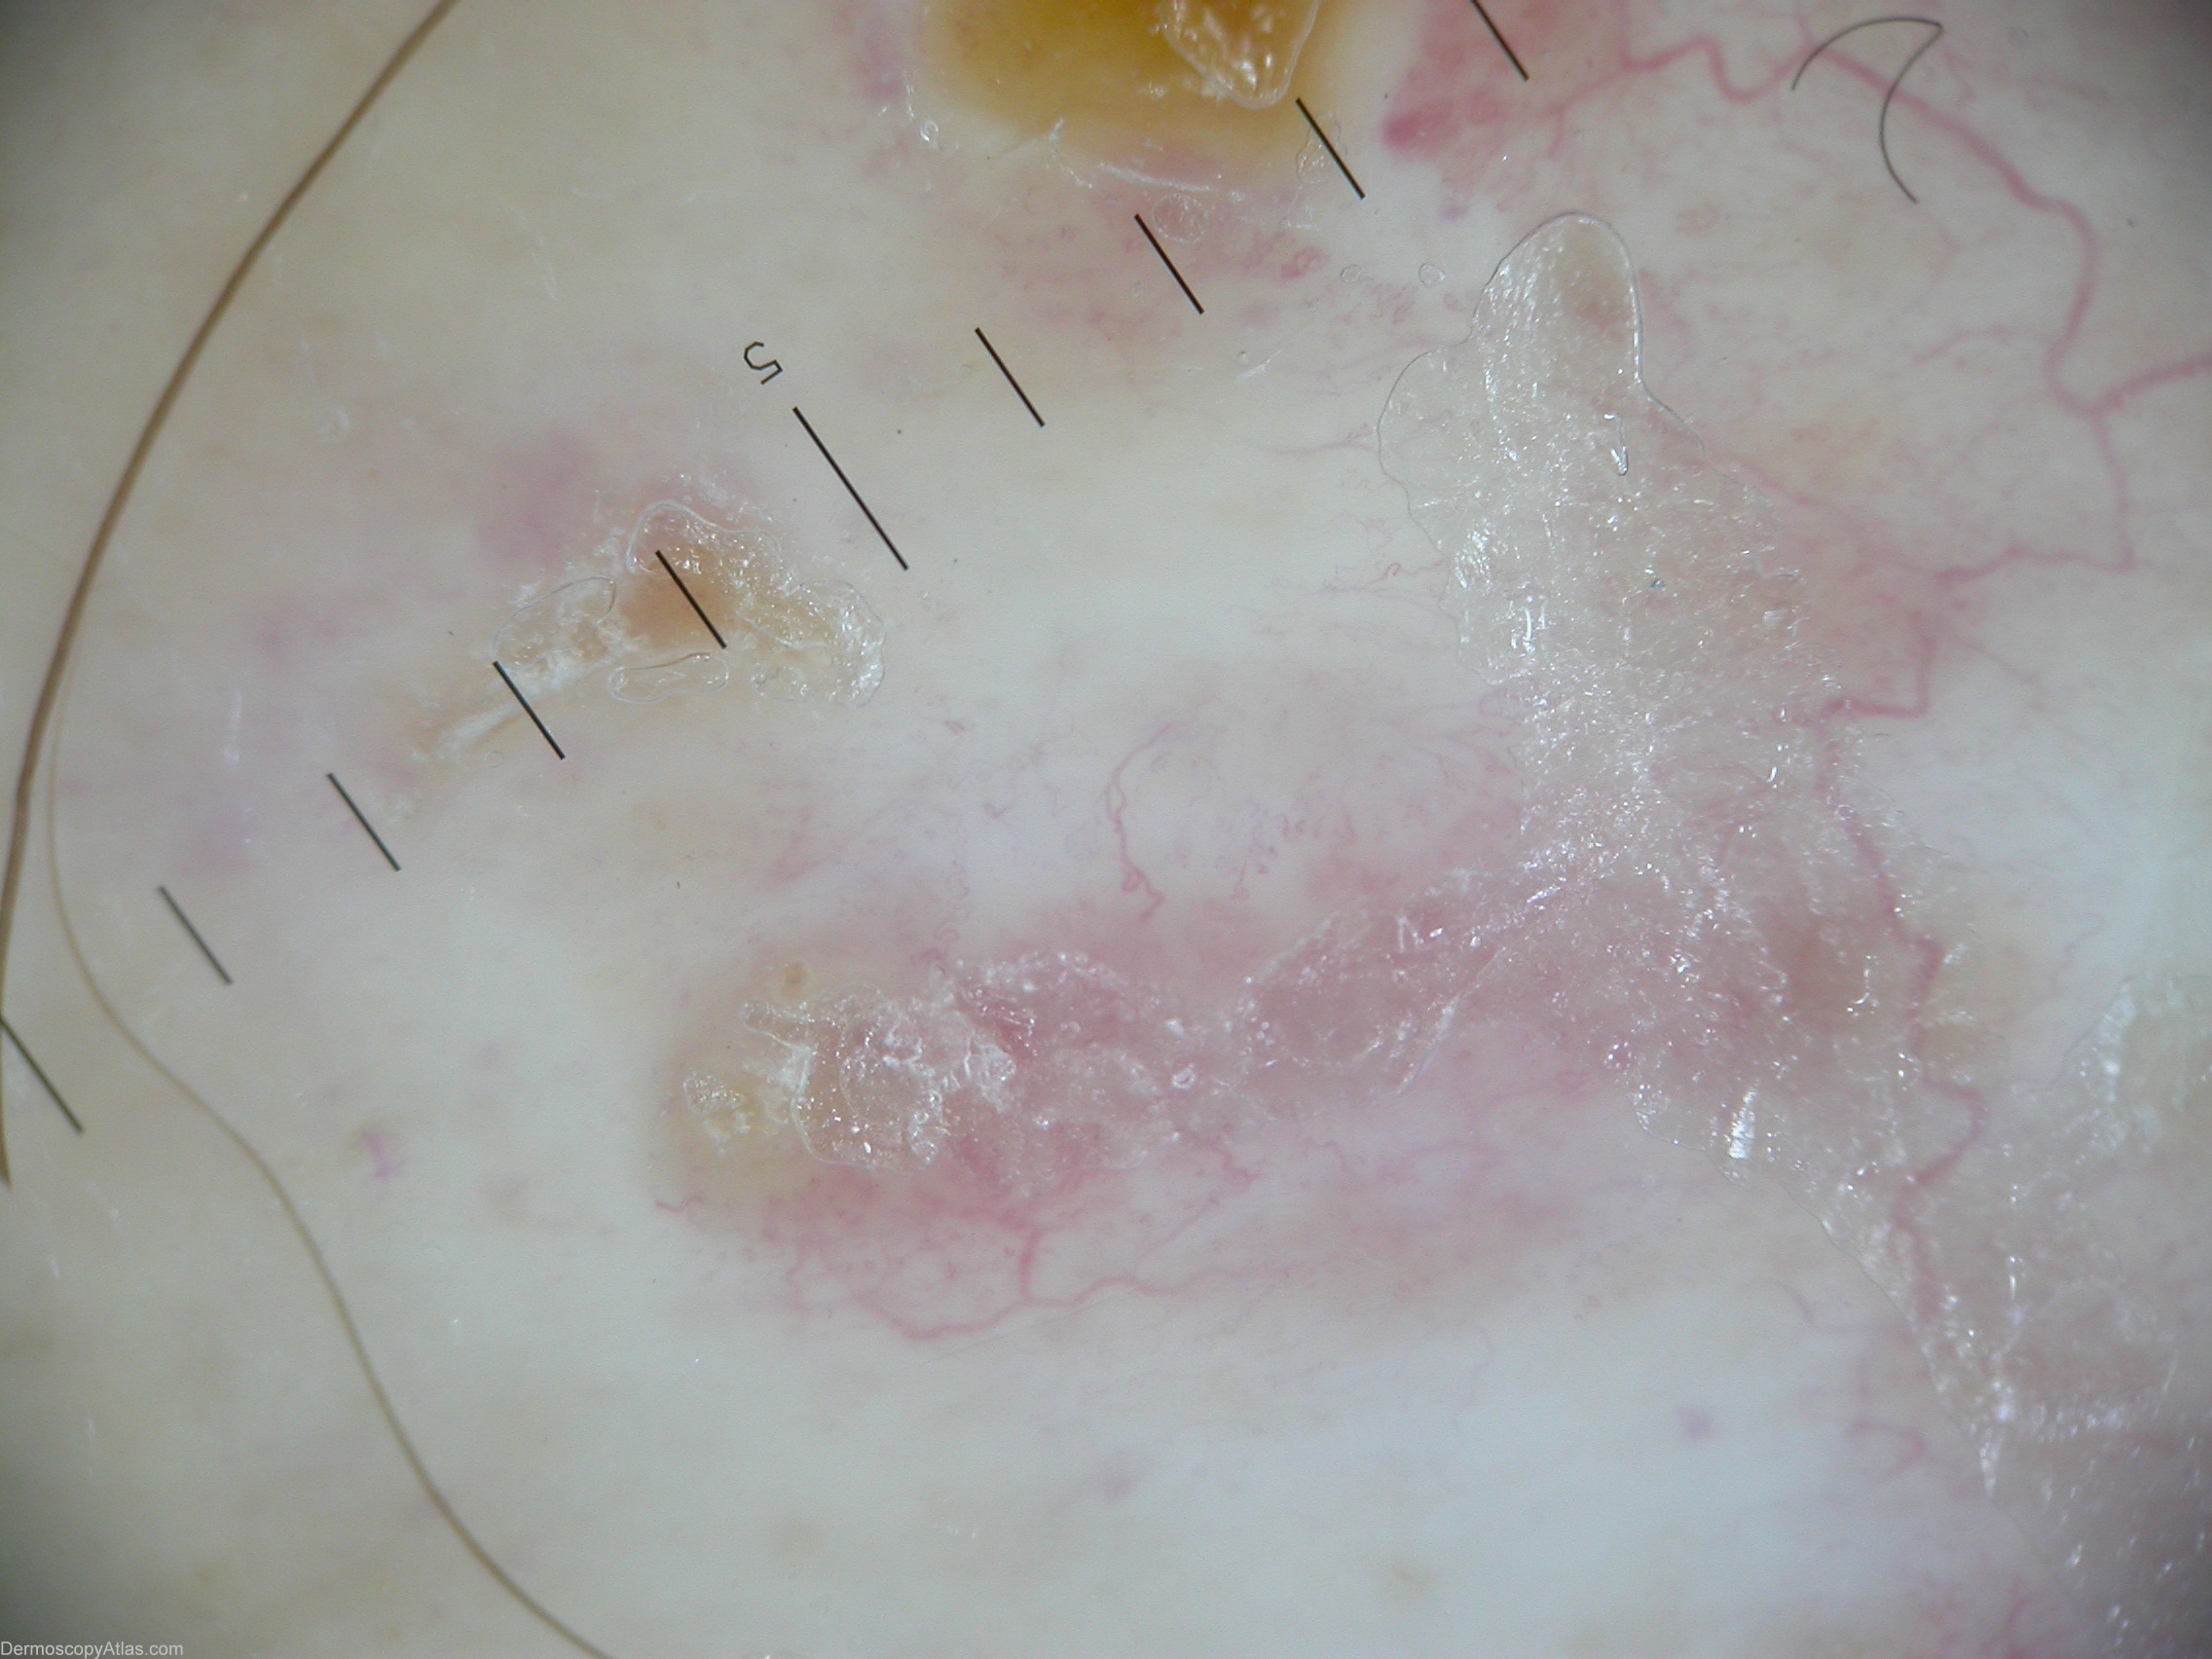

Diagnosis: Necrobiosis lipoidica

Description: Accentuated arborizing vessels with pearl-white areas of fibrosis.

History: This plaque continued to expand slowly one year after it appeared on the shin of a 49 year old nondiabetic woman. A biopsy showed altered collagen and granulomatous inflammation typical of necrobiosis lipoidica. Dermascopic picture of necrobiosis lipoidica could be described by accentuated arborizing vessels with pearl-white areas of fibrosis.